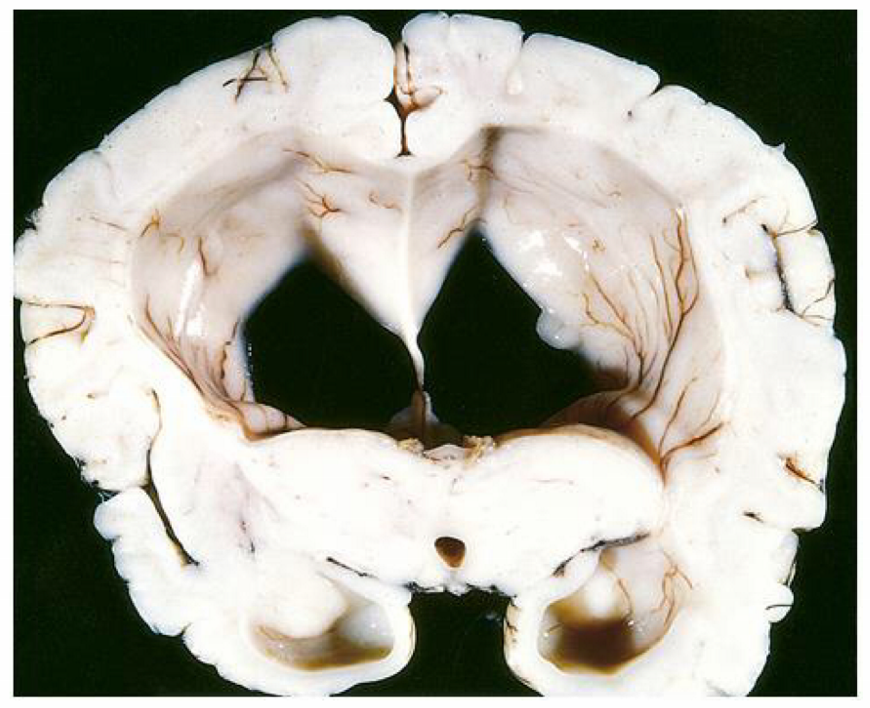

the condition seen in the image originates from \_\_\_\_

the condition seen in the image originates from **glial cells/astrocytes**

there is a ____ appearance on gross in the condition seen in the image

there is a **butterfly** appearance on gross in the condition seen in the image

histology of the condition seen in the image would show a central ____ surrounded by \_\_\_\_

histology of the condition seen in the image would show a **central area of necrosis** surrounded by **pseudo-palisading of the malignant cells**

presentation of the condition seen in the image is recurrent ____ that is worse in the ____ and while \_\_\_\_

presentation of the condition seen in the image is recurrent **headaches** that is worse in the **mornings** and while **straining**

describe the presentation of the condition seen in the image

sudden onset recurrent headaches that are worse in the mornings & while straining seizures papilledema contralateral hemiparesis

\_\_\_\_ is a tumor marker for the condition seen in the image

**GFAP** is a tumor marker for the condition seen in the image

the condition in the image has a better prognosis if there is a mutation is in ____ or \_\_\_\_

the condition in the image has a better prognosis if there is a mutation is in **IDH-1** or **IDH-2**

list factors that lead to a good prognosis of the condition seen in the image

younger (-) EGFR (+) IDH-1, IDH-2 (+) p53 (+) MGMT methylation

list 3 factors that make the condition seen in the image have a poor prognosis

infiltrate unresectable resistant to treatment